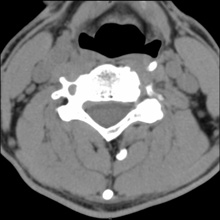

Für das Bild der Woche wurde dieses Mal eine besondere Vorrichtung benutzt. Auf Grund ständiger Schmerzen im rechten Oberarm suchte ich meinen Hausarzt auf. Nach einer kurzen Untersuchung vermutet er etwas im Halswirbelbereich und schickte mich zum Radiologen. Dort wurde eine Computer Tomografie (CT) gemacht. Die Bilder erhielt ich auf einer CD für meinen Hausarzt.

Und weil ich nun mal neugirig bin, legte ich die CD in das Laufwerk meines Rechners und siehe da, es tat sich was. Auf der CD ist ein Viewer, mit dem man sich die Ergebnisse der CT ansehen kann. Sieht schon toll aus, nur deuten kann ich es nicht. Fahren Sie mal mit der Maus in das Bild. Dann bekommen Sie einen kleinen Eindruck von den verschiedenen Schichten. Mal sehen, was mein Hausarzt in der nächsten Woche dazu sagt....